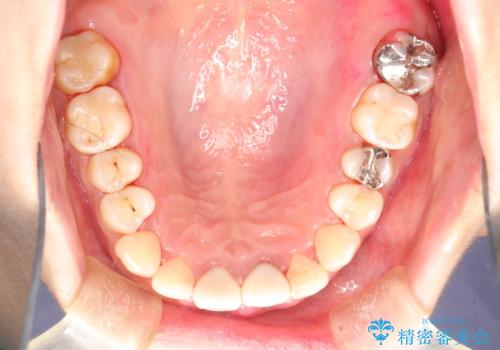

治療途中

かなり久しぶりの歯科医院との事で、全体的に古くからの歯垢・歯石が多く付着していたため、自費クリーニング(PMTC)60分コース・歯周ポケット検査(保険適応)を行いました。